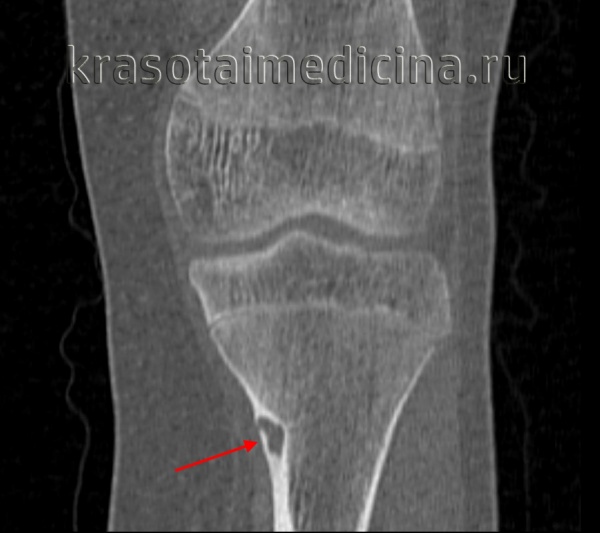

Остеоидная остеома

Характеристика

Может располагаться на любых костях, кроме грудины и костей черепа. Типичная локализация остеоидной остеомы – диафизы (средние части) и метафизы (переходные части между диафизом и суставным концом) длинных трубчатых костей нижних конечностей. Около половины всех остеоидных остеом выявляется на большеберцовых костях и в области проксимального метафиза бедренной кости. Развивается в молодом возрасте, чаще наблюдается у мужчин. Сопровождается нарастающими болями, которые появляются еще до возникновения рентгенологических изменений. Примерно 10% от общего числа случаев составляют остеоидные остеомы позвонков.

Диагноз остеоидной остеомы выставляется на основании характерной рентгенологической картины. Обычно из-за своего расположения такие опухоли лучше видны на рентгеновских снимках по сравнению с обычной остеомой. Однако в ряде случаев также возможны затруднения из-за малого размера остеоидной остеомы или ее локализации (например, в области позвонка). В таких ситуациях для уточнения диагноза используется компьютерная томография.

В ходе рентгенологического исследования под кортикальной пластинкой выявляется небольшой округлый участок просветления, окруженный зоной остеосклероза, ширина которой увеличивается по мере прогрессирования заболевания. На начальном этапе определяется четко видимая граница между ободком и центральной зоной остеомы. В последующем эта граница стирается, так как опухоль подвергается обызвествлению.

При гистологическом исследовании остеоидной остеомы обнаруживается остеогенная ткань с большим количеством сосудов. Центральная часть остеомы представляет собой участки образования и разрушения кости с причудливо переплетающимися балочками и тяжами. В зрелых опухолях выявляются очаги склерозирования, а в «старых» - участки настоящей волокнистой кости.

Дифференциальный диагноз остеоидной остеомы проводится с ограниченным склерозирующим остеомиелитом, рассекающим остеохондрозом, остеопериоститом, хроническим абсцессом Броди, реже – опухолью Юинга и остеогенной саркомой.

Лечением остеоидной остеомы обычно занимаются травматологи и ортопеды. Лечение только хирургическое. В ходе операции выполняется резекция пораженного участка, по возможности – вместе с окружающей его зоной остеосклероза. Рецидивы наблюдаются очень редко.